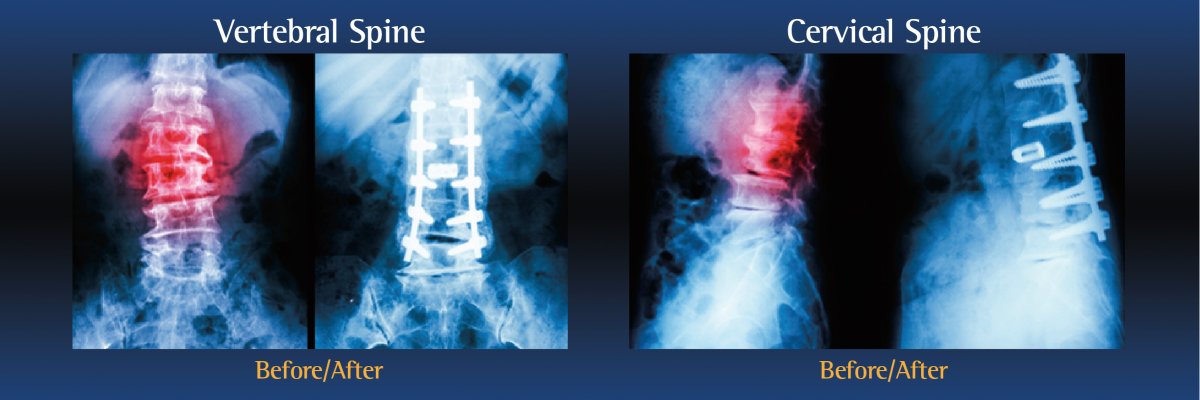

During the operation, an incision is made in the neck, back or abdomen. Bone, debris, bone growths, lamina, and/or the damaged vertebral disc may be cleared from the spine, creating more space and relieving pressure on the spinal nerves. The surgeon will then take the proper steps to correct the patient’s specific problem.

Bone grafts may then be placed in the space or along the side of the spine. If additional support is needed, metal hardware (including pins or screws), may be used to steady the spine as it fuses. The incision is closed to finalize the surgery.

The grafts will grow into solid bone, fusing together the vertebrae. Patients may have to wear a back brace post-surgery, which will support your spine and keep the vertebrae from moving as the grafts fuse together.